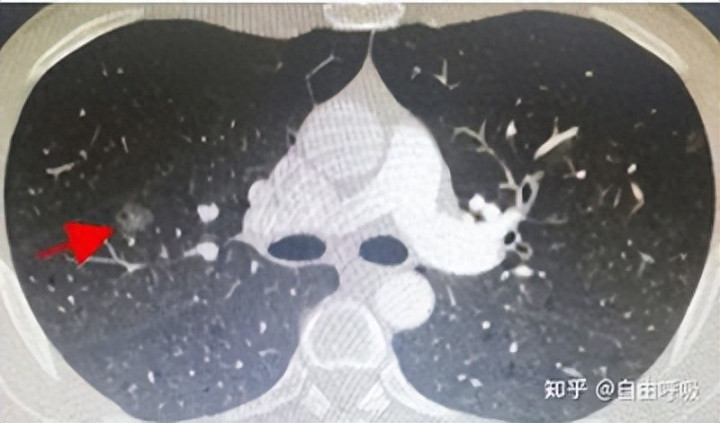

这个结节位于右肺上叶,9mm磨玻璃结节,密度为-600左右,可以说是一个纯磨玻璃结节。而且患者在此之前的肺CT中并未提示结节中有空泡。

如果单纯靠空泡征就判断这个结节是恶性的要切除,理由显然是不充分的。

虽然“空泡征”是提示肺磨玻璃结节为肺癌的一个标志性征象,但需要有个前提:持续存在。

即持续存在(一般认为要持续3个月以上)的含有空泡征的肺磨玻璃结节,肺癌的可能性才比较大